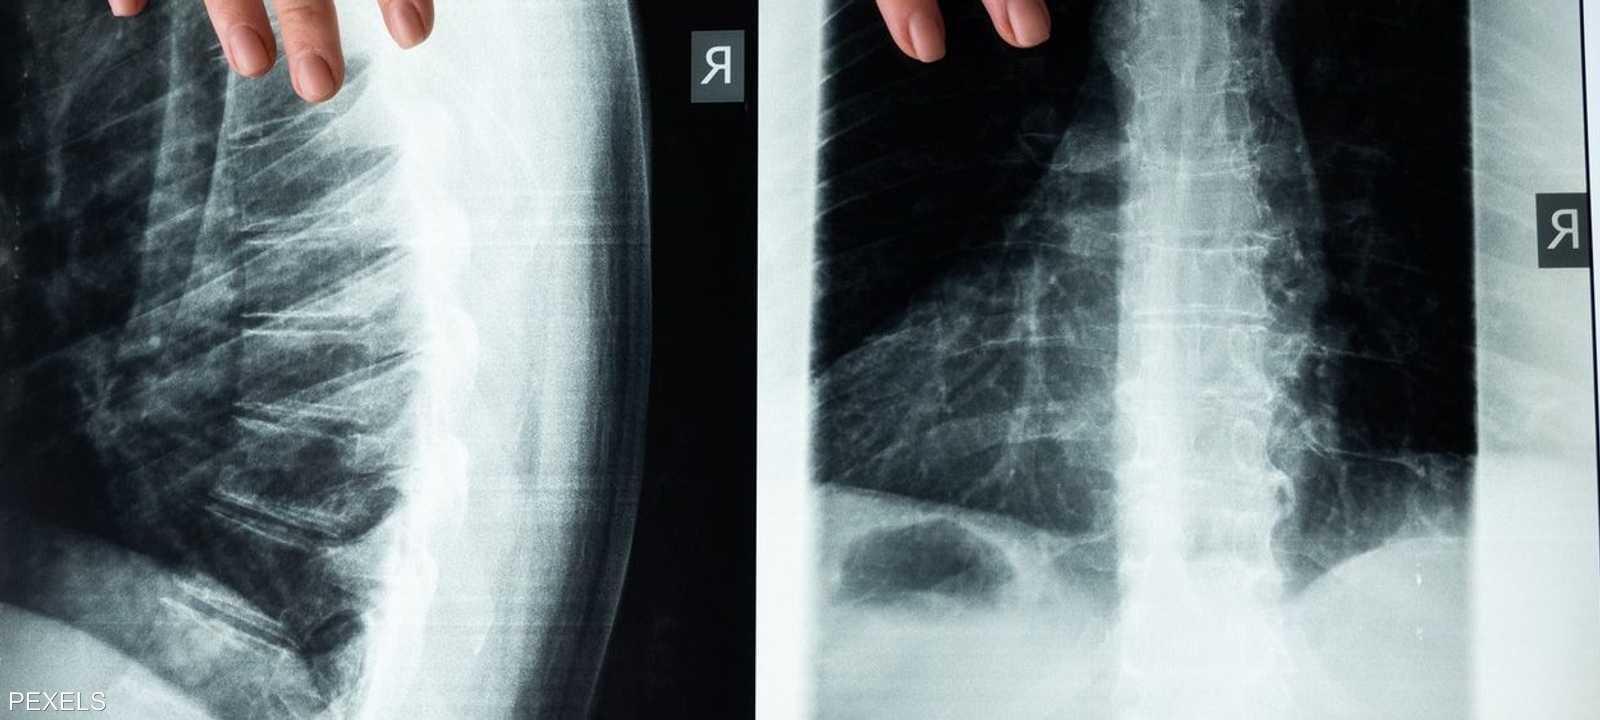

تطور طبي ثوري، كشفته دراسة أميركية جديدة قد توفر علاجا جديدا للمصابين بالشلل والحالات المتعلقة بالحبل الشوكي.

وطور باحثو جامعة نورث ويسترن الأميركية علاجا جديدا عن طريق الحقن يستخدم "الجزيئات الراقصة" لعكس الشلل وإصلاح الأنسجة بعد إصابات الحبل الشوكي الشديدة.